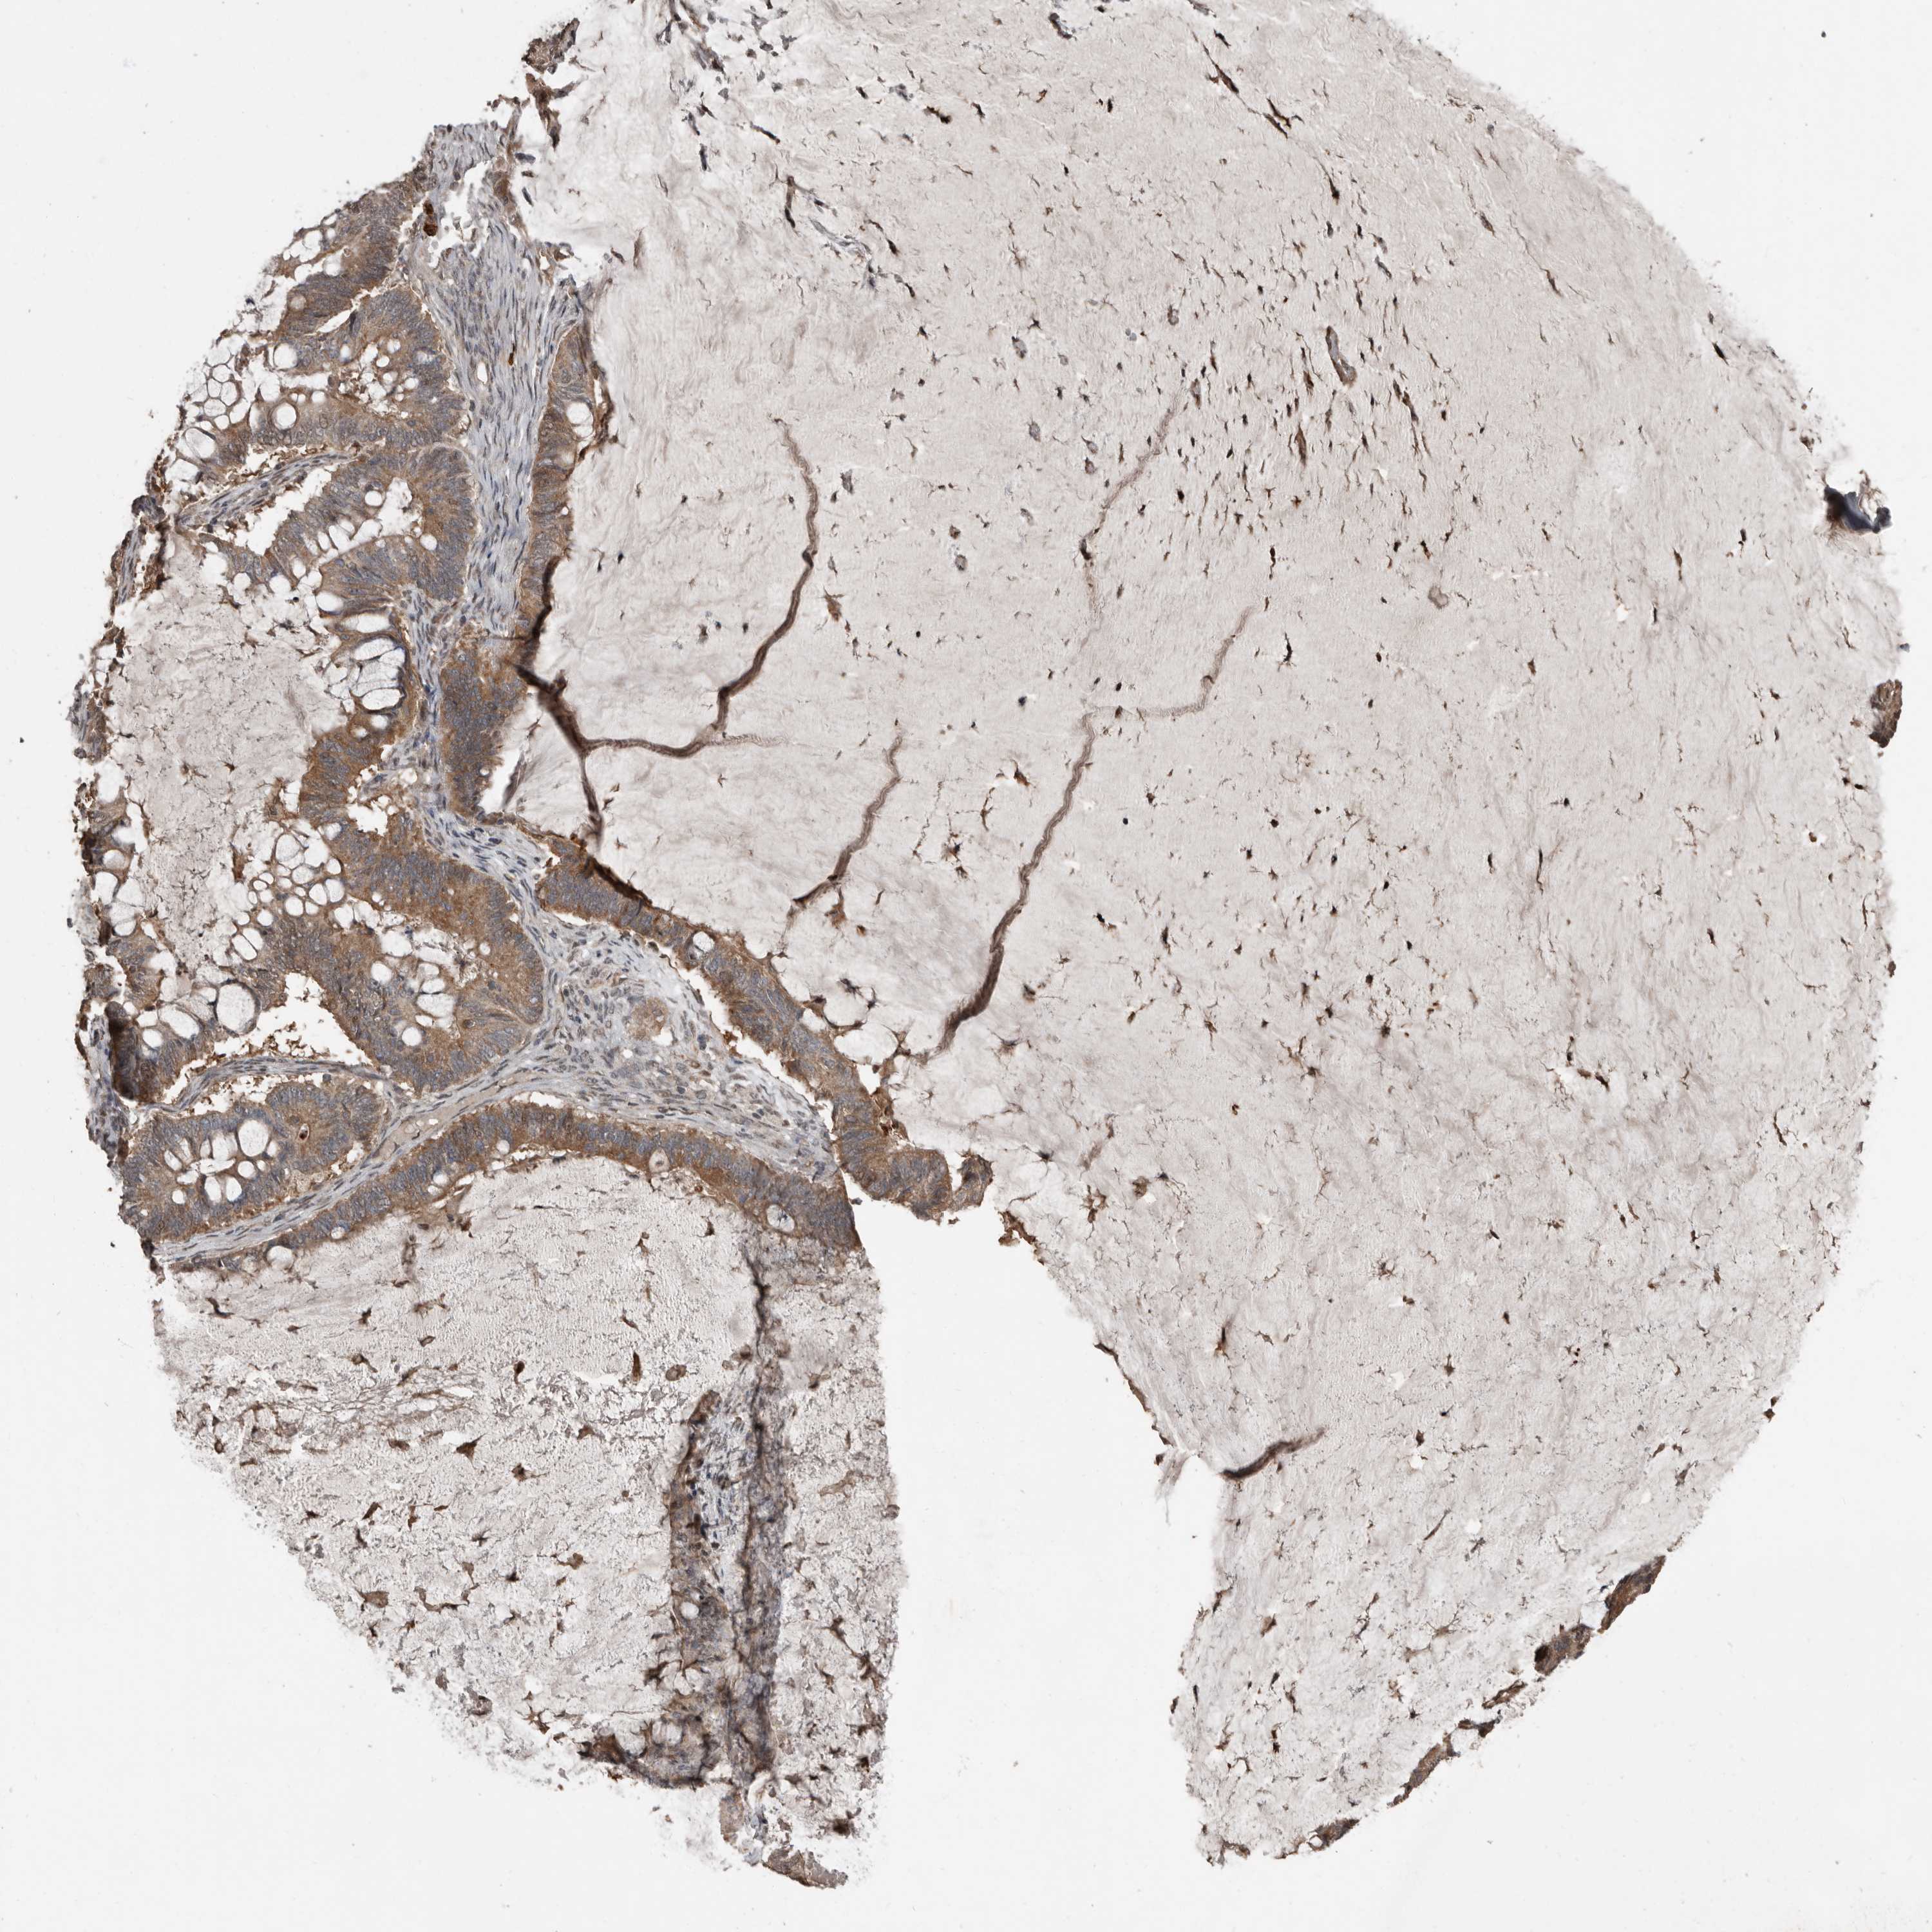

OVARIAN CANCER - Protein expressioni

A mouse-over function shows sample information and annotation data. Click on an image to view it in a full screen mode. Samples can be filtered based on level of antibody staining by selecting one or several of the following categories: high, medium, low and not detected. The assay and annotation is described here.

Note that samples used for immunohistochemistry by the Human Protein Atlas do not correspond to samples in the TCGA dataset.

Antibody stainingi

Antibody staining in the annotated cell types in the current human tissue is reported as not detected, low, medium, or high, based on conventional immunohistochemistry profiling in selected tissues. This score is based on the combination of the staining intensity and fraction of stained cells.

Each image is clickable and will lead to virtual microscopy that enables deeper exploration of all samples and also displays staining intensity scores, fraction scores and subcellular localization as well as patient and tissue information for each sample.

Antibody HPA026509

Cystadenocarcinoma, serous, NOS

Carcinoma, endometroid

Cystadenocarcinoma, mucinous, NOS

Carcinoma, NOS